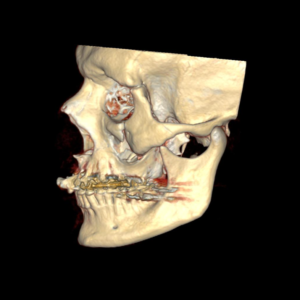

- Fraturas dos maxilares e órbita;

A maioria dos ferimentos simples na pele pode ser tratada com anestesia local, limpeza da lesão e sutura. As fraturas da face e lesões complexas são tratadas sob anestesia geral. Os ossos quebrados são restaurados utilizando-se, geralmente, mini-placas e parafusos de titânio (que são biocompatíveis e não sofrem rejeição) que facilitam a recuperação e cicatrização óssea e dos tecidos